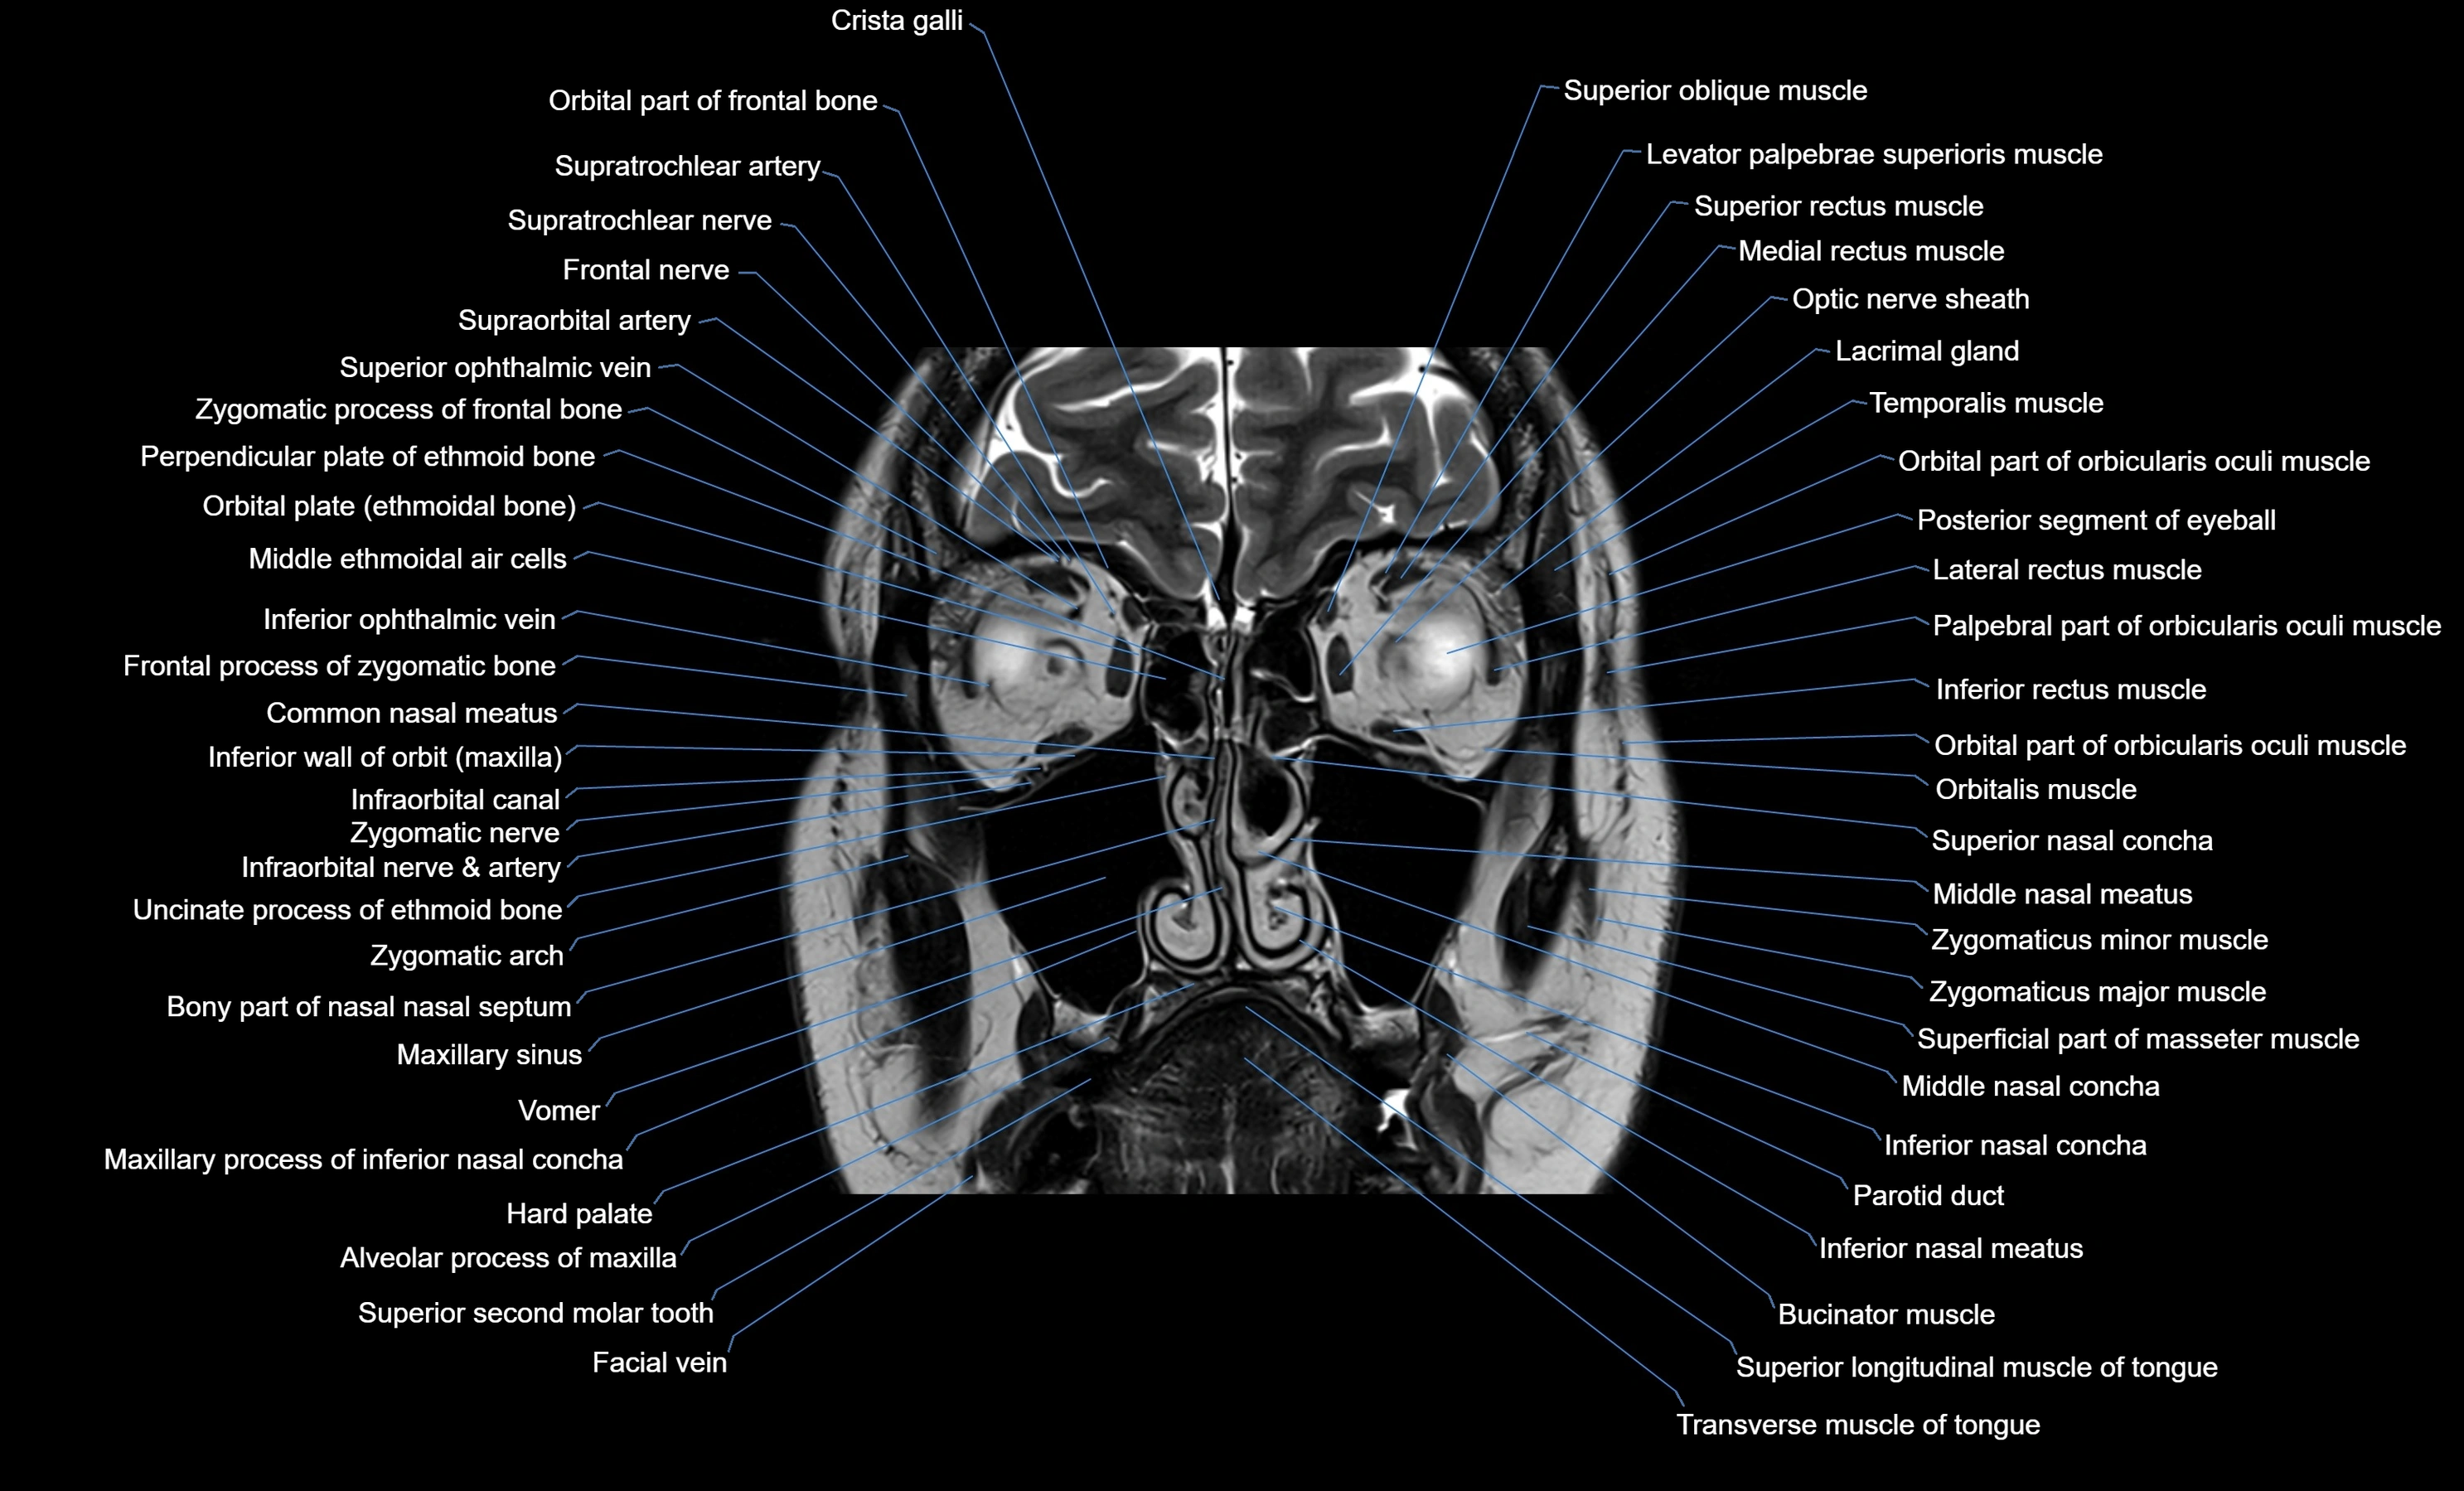

MRI images